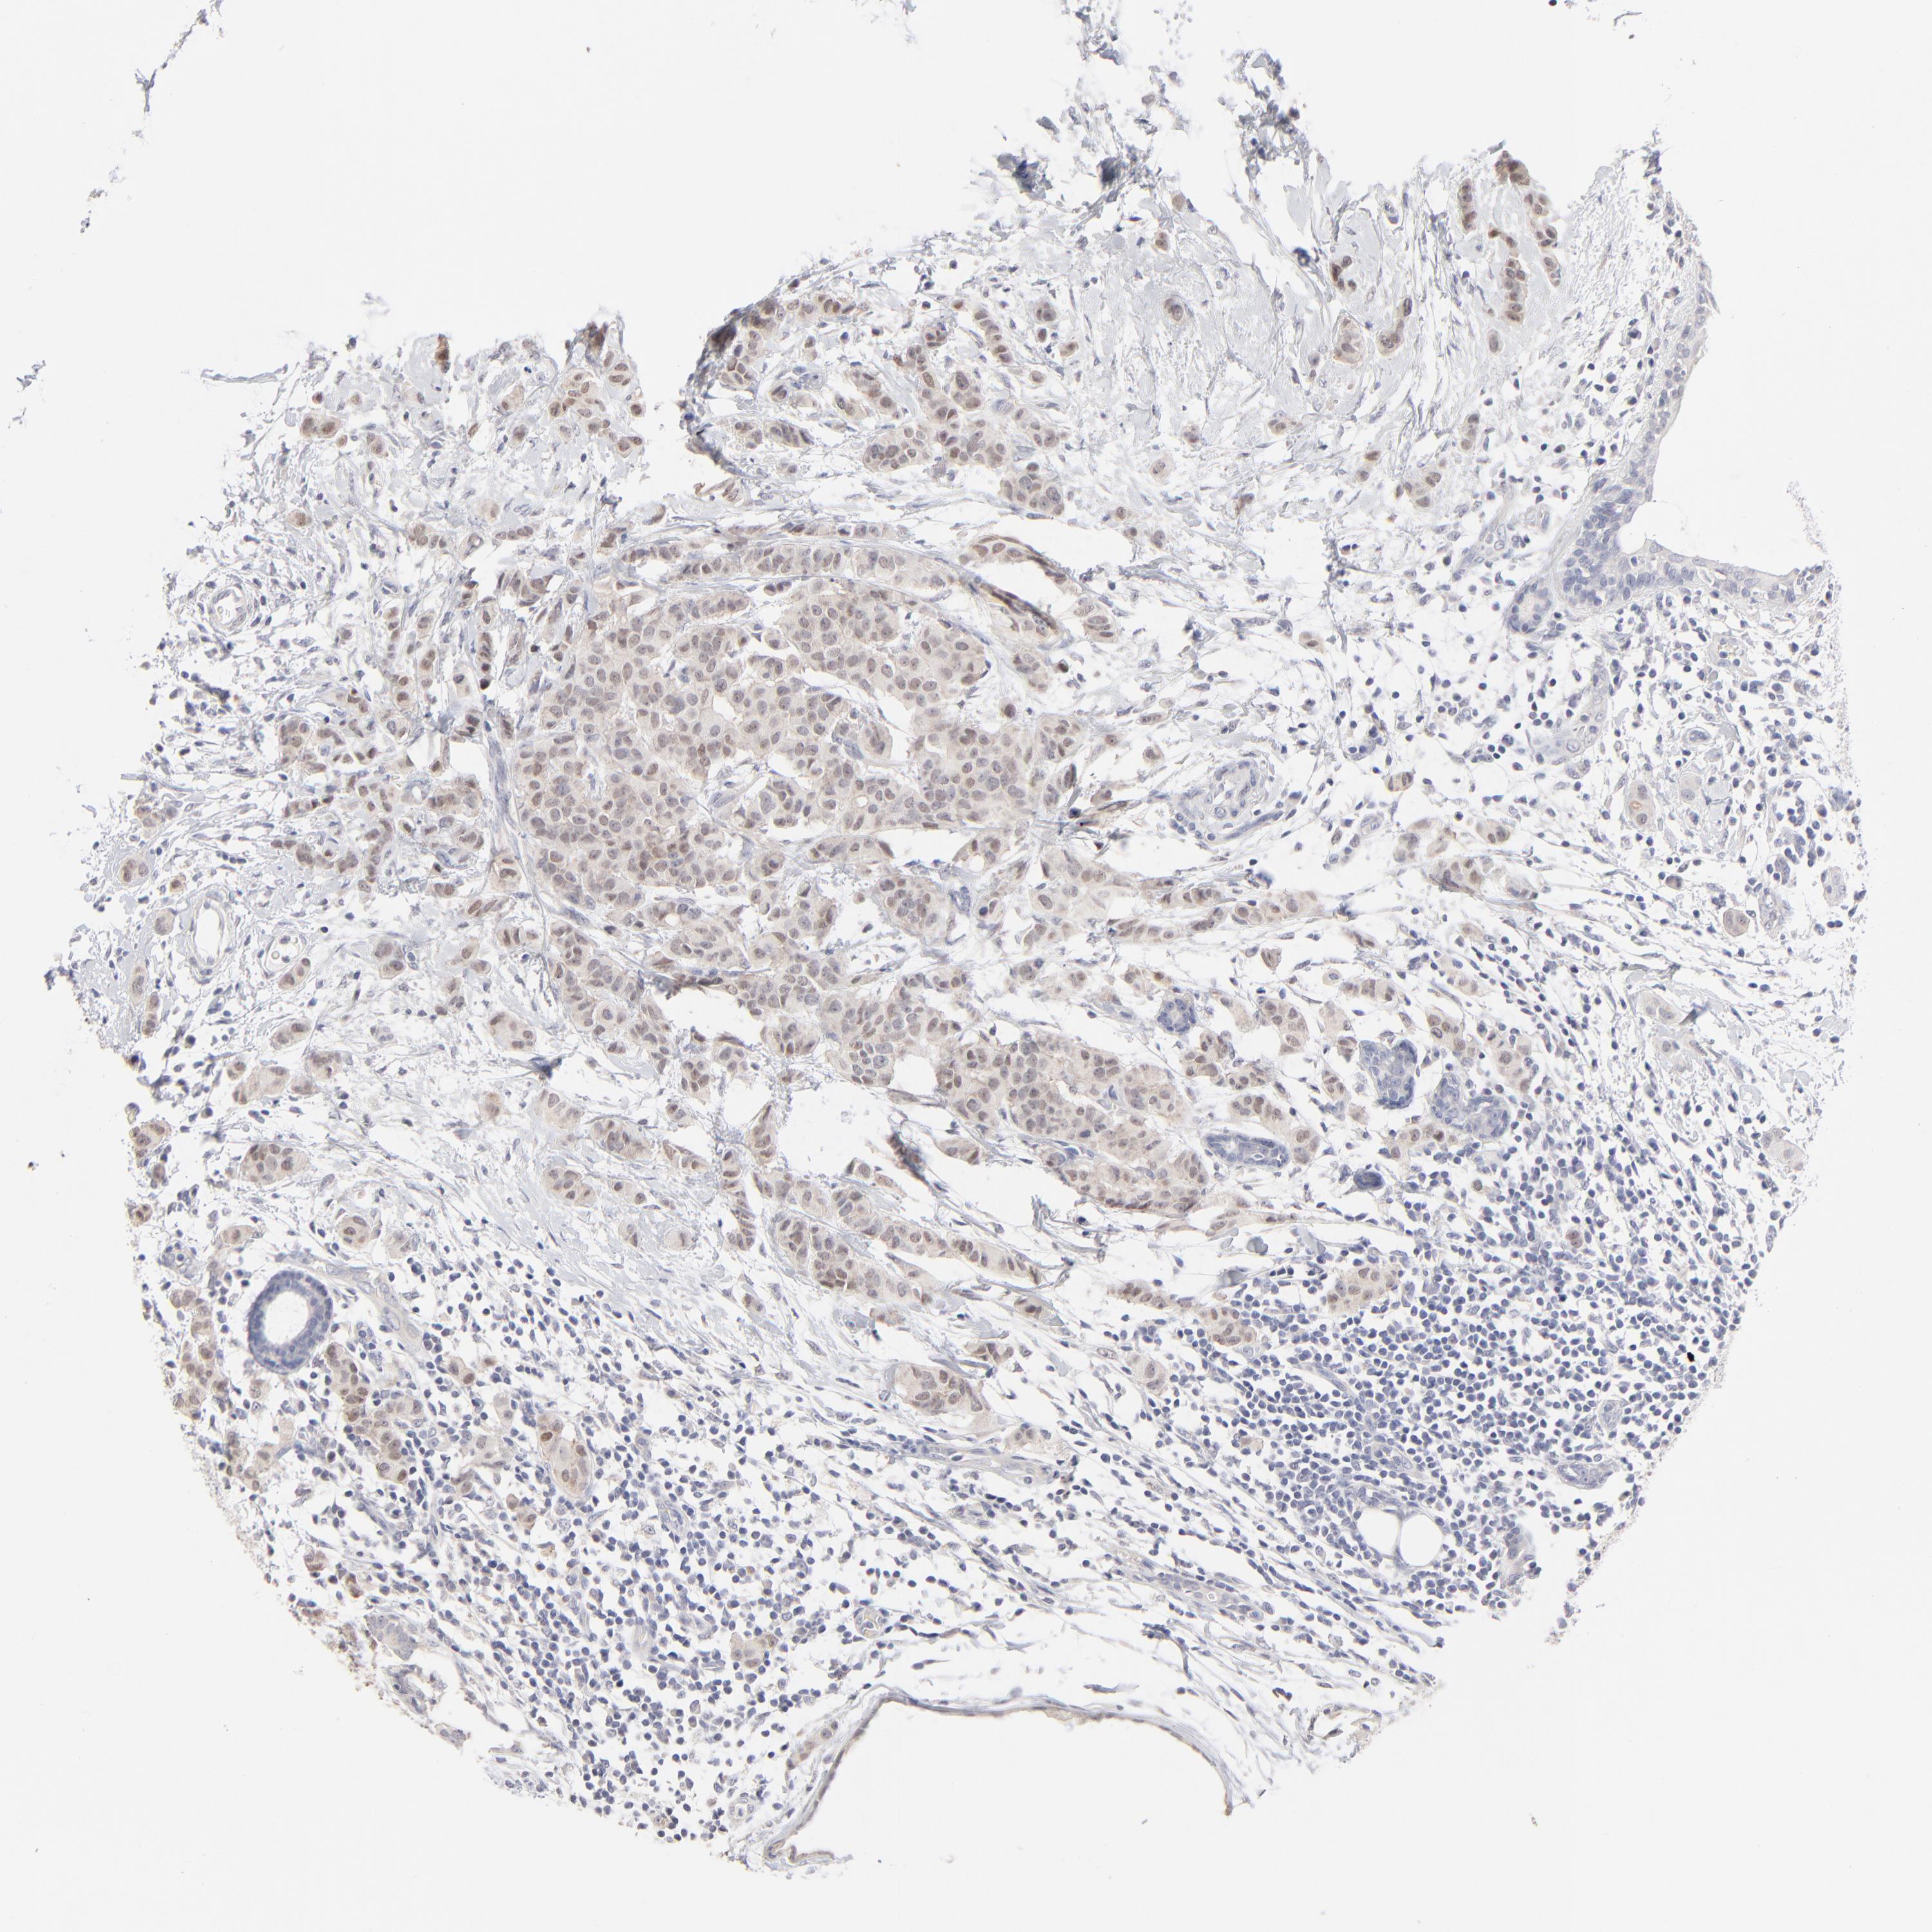

CANCER BREAST CANCER Show tissue menu

BRCA TCGA BRCA VALIDATION PROTEIN EXPRESSION

ANTIBODIES

AND

VALIDATION